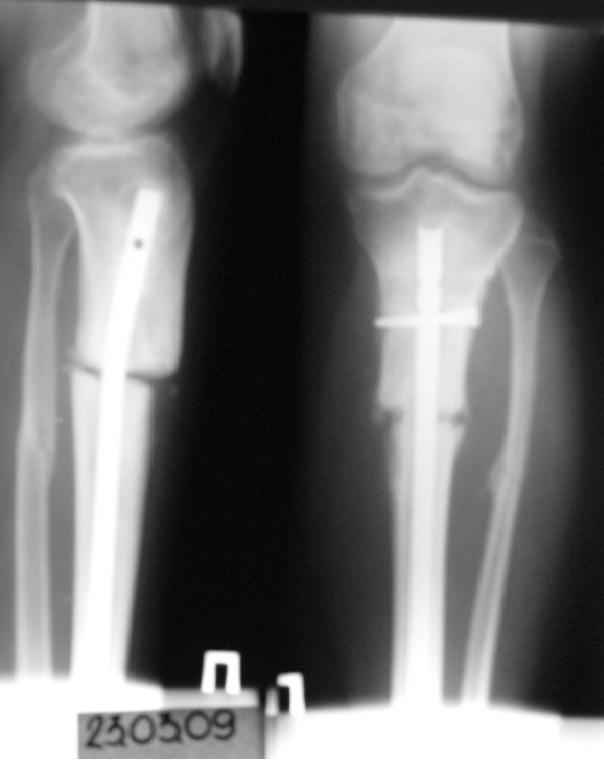

История следующая: женщина (медработник)сбита машиной 7.06.08 - о.перелом обоих костей голени в/3 со смещением. В ПДО ПХО раны,вытяжение за пяточную кость. После заживления раны 20.06.08 выполнен остеосинтез блокирующем стержнем. в течение первого месяца после травмы сохранялась субфебрильная температура на фоне приема антибиотиков. Затем температура стабилизировалась.Б-ая как положено ходила в гипсе на костылях. На контрольных рентгенограммах консолидация не достигалась, иммобилизация продлевалась. Пациентка на себе опробовала все препараты костной регенерации. В марте удален один из фиксирующих винтов. На сегодняшний день идет 11 мес. после травмы. Решается вопрос о инвалидности. Буду благодарен за предложения по дальнейшему ведению больной. Операция?

-зачем так глубоко погружать гвоздь - не боитесь проблем при удалении?

- почему блокирующие винты введены снаружи - рана или другая причина?

- куда, вернее как исчезло смещение на передне-задней проекции?

И наконец, судя по снимкам - гвоздь SIGN, или я ошибаюсь? У нас есть опыт их применения при похожих переломах (8-10 случаев) - все срастались не менее 7-8 месяцев, часто требовали динамизации и пр.

Не показан нижний конец гвоздя. Винты надо было убирать из него, зачем из верхнего-то отломка.

Остеосинтез сделан был небезупречно. Гвоздь SIGN и так не самый лучший выбор для такого перелома. Но можно было сделать не хуже, чем каким-то специализированным для проксимального отдела. Следовало использовать трансмедуллярные (Poller) винты. То есть искусственно сузить канал в центральном отломке.

Судя по изменению положения гвоздя в послеоперационном периоде (хотя и в благоприятную сторону) нестабильность была очевидна. И не стоило

пытаться решить проблему гипсом, надо было сразу делать ревизионный остеосинтез. В итоге пациент бы не потерял год на лечение.

Сейчас надо перештифтовать. При удалении взять посев. Не просто рассверлить старый канал и поменять гвоздь на больший, а устранить все смещения при помощи отклоняющих винтов. Рассверлить надо. Малоберцовую, наверно, лучше пересечь внизу.

На рентгенограмме несоответствия кортикальной аппозиции в виде потерянного сегмента и пластическая деформация малоберцовой, это знак оставленного ротационного смещения во время операции.

Движение вокруг проксимального гвоздя означает разгибательно-сгибательную нестабильность в проксимальной части большеберцой.

При применении традиционной интрамедуллярной техники проблему короткого импланта решают дополнительным на 15-20 мм заглушкой. Но, возможности гвоздей от SIGN ограничены и они рассчитаны для ортопедов из третьего мира, где вообще отсутствует рентгенологические возможности во время операции.

Блокировка шурупов, которая сделана с наружной стороны с большим риском для малоберцовой, не создает двойную кортикальную стабильность. Для облегчения нахождения отверстия без рентгена, входящее кортикальное отверстие делается большего диаметра и проведенный шуруп держится только за дальний кортекс.

Со временем появляется нестабильность и даже отлично подобранный диаметр гвоздя в середине не гарантирует хорошую фиксацию. Дополнительные гипсовые повязки не создадут стабильность, лучше сужение канала с помощи блокирующих шурупов или спиц.